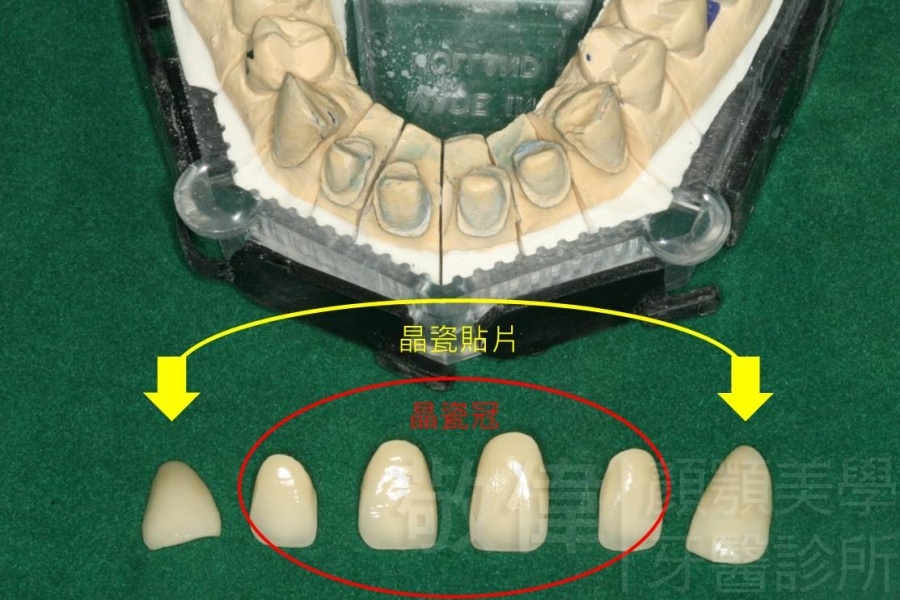

| 8 | 前牙美容 | 快速矯正之美容晶瓷貼片及晶鑽瓷冠 | ||